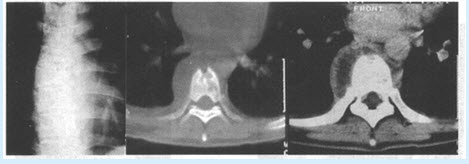

患者,男,56岁。因背部疼痛2个月入院;查体:胸椎T~T棘突和椎旁有压痛,胸椎活动受限。体温38.4℃,X线平片和CT见下图。